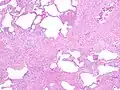

The histologic hallmarks of UIP, as seen in lung tissue under a microscope by a pathologist, are interstitial fibrosis in a "patchwork pattern", honeycomb change and fibroblast foci (see images below).[6][7]